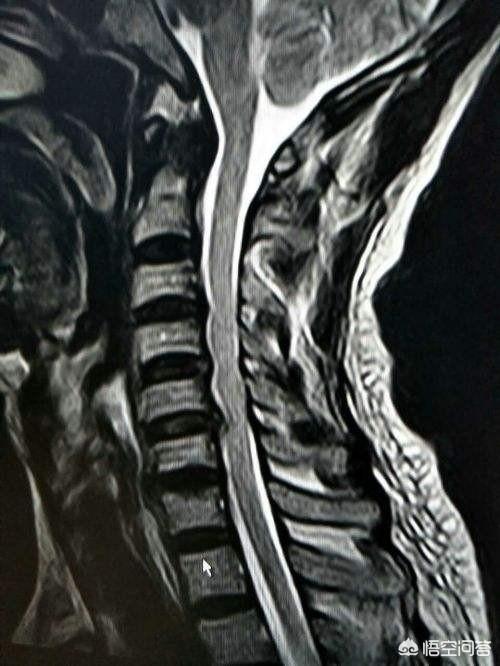

Une hernie discale cervicale appuyant sur une racine nerveuse peut provoquer des douleurs à l'épaule.

Lorsque la colonne cervicale présente une hernie du clavier ou des ostéophytes qui provoquent la formation de moelle osseuse et compriment la zone d'articulation.La douleur à l'épaule survient lorsque la racine nerveuse n'est pas en place, et cette douleur a une caractéristique qui est principalement de type piqûre d'épingle, comme une décharge électrique, et n'est généralement pas corrélée avec le mouvement de l'épaule.En d'autres termes, cette douleur existe quel que soit l'angle de mouvement de l'épaule. Au contraire, il peut y avoir une relation entre cette douleur et l'activité de la colonne cervicale, par exemple une inclinaison cervicale excessive vers l'arrière ou une inclinaison de la tête vers l'avant peuvent irriter les racines nerveuses et provoquer une aggravation de la douleur.

En d'autres termes, la douleur se manifeste au niveau de l'épaule, mais le problème se situe au niveau de la colonne cervicale !

Si l'on soupçonne que la colonne cervicale est à l'origine de la douleur à l'épaule, il est nécessaire de procéder à un examen.IRM de la colonne cervicaleVoici quelques exemples permettant de s'assurer qu'une hernie discale cervicale ou une anomalie de la structure osseuse est à l'origine d'une compression nerveuse. Si elle s'accompagne d'une faiblesse des épaules ou des membres supérieurs, il peut même être nécessaire d'effectuerélectromyographieL'examen permet de déterminer si les nerfs ont été endommagés. Possibilités de traitementdonner ou recevoir de l'acupuncture et de la moxibustionVoici quelques-unes des questions les plus importantes qu'il convient d'aborder pour parvenir à une bonne gestion des ressources humaines.tirer (un chariot)Si la douleur est intense, vous pouvezAnalgésiques et anti-inflammatoires orauxComme la plupart de ces douleurs sont dues à un œdème des racines nerveuses, il est possible de prendre des médicaments par voie orale.Médicaments anti-oedème,Vous pouvez également suivre des séances de physiothérapie, comme la stimulation électrique transcutanée des nerfs, et vous obtiendrez généralement un soulagement après un traitement systématique. Cette période peut durer de 1 à 2 semaines dans la phase aiguë, et il faudra environ trois mois pour obtenir un soulagement progressif.Les patients doivent être préparés et ne pas être pressés, car ce type de problème nécessite de prendre son temps.。